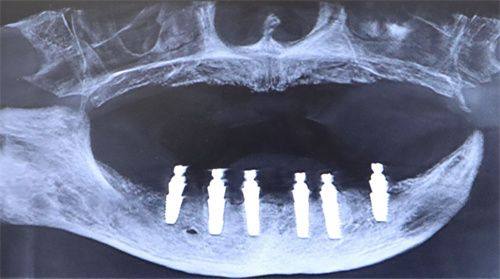

尽管并发症并不常见,但一些患者在种植牙5年后可能会遇到问题。比如种植体周围炎,这是一种炎症反应,可能会导致种植体周围骨头的丧失。不过,只要定期进行专精检查,就可以及早发现并处理这类问题。另外,长期使用后,部分患者可能需要进行一些小修复,如更换牙冠或紧固松动的零件。这些小问题只要及时处理,一般不会影响种植牙的正常使用。